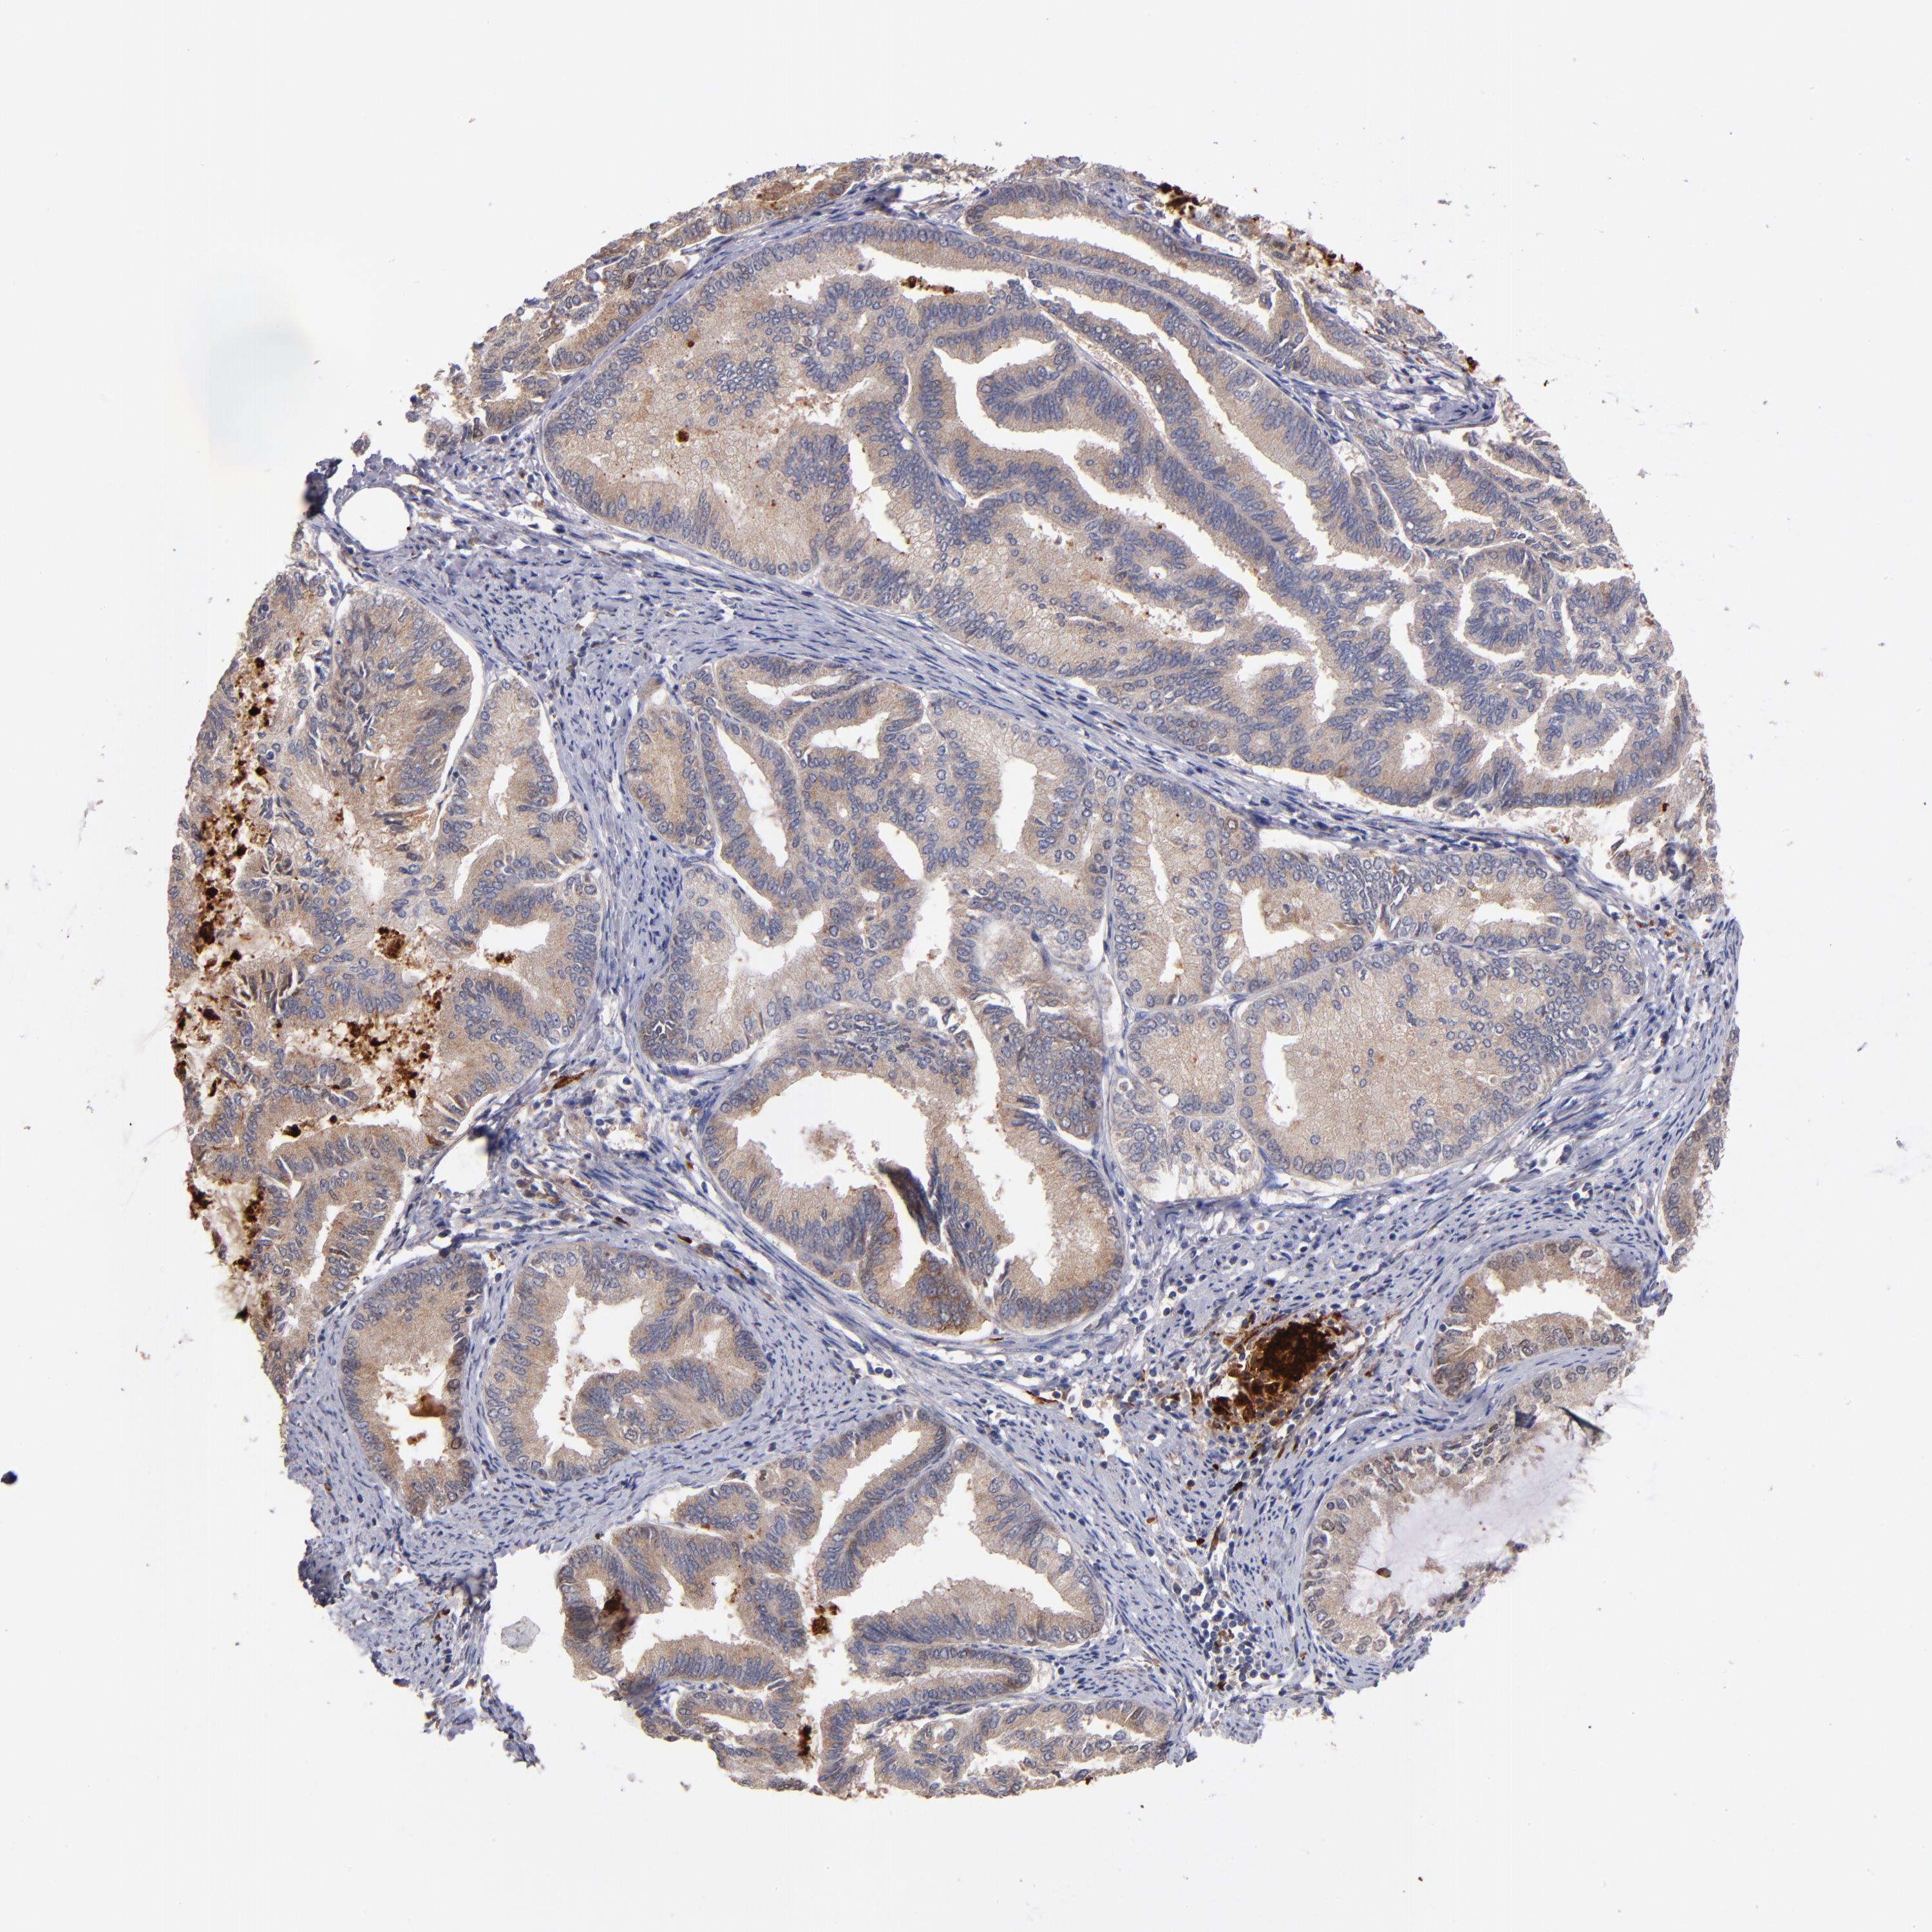

ENDOMETRIAL CANCER - Protein expressioni

A mouse-over function shows sample information and annotation data. Click on an image to view it in a full screen mode. Samples can be filtered based on level of antibody staining by selecting one or several of the following categories: high, medium, low and not detected. The assay and annotation is described here.

Note that samples used for immunohistochemistry by the Human Protein Atlas do not correspond to samples in the TCGA dataset.

Antibody stainingi

Antibody staining in the annotated cell types in the current human tissue is reported as not detected, low, medium, or high, based on conventional immunohistochemistry profiling in selected tissues. This score is based on the combination of the staining intensity and fraction of stained cells.

Each image is clickable and will lead to virtual microscopy that enables deeper exploration of all samples and also displays staining intensity scores, fraction scores and subcellular localization as well as patient and tissue information for each sample.

Antibody HPA001825

Antibody CAB003857

Staining

High

Medium

Low

Not detected

Intensity

Strong

Moderate

Weak

Negative

Quantity

>75%

75%-25%

<25%

None

Location

Nuclear

Cytoplasmic/membranous

Cytoplasmic/membranous,nuclear

Adenocarcinoma, NOS

Neoplasm, malignant, NOS